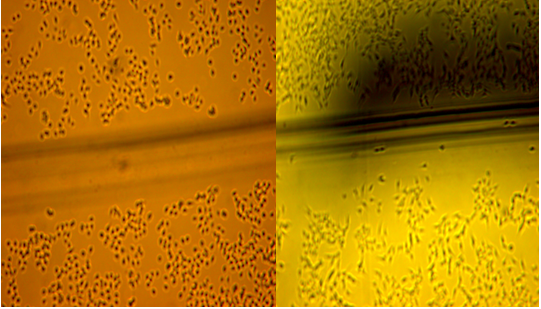

FU+小分子果胶下面几幅为划痕实验,结果证明改性果胶和5-氟尿嘧啶联合使用可以有效抑制肿瘤细

胞的远端转移情况。

Fu+小分子果胶组 control组

小分子果胶组 5- Fu组